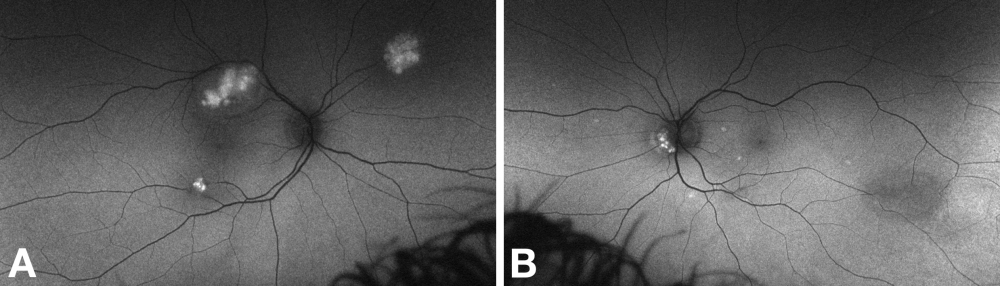

Fluorescein Angiography

Fundus fluorescein angiography demonstrates early blockage of background choroidal fluorescence, a plexus of capillaries within the tumor, and late leak (hyperfluorescence, gradually increasing in intensity and extent).[13][24] Angiography may demonstrate additional tumors that are not apparent clinically.